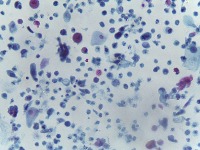

Medical Diagnostics: This model can be used in the healthcare industry to provide high-speed automated analysis of pathology slides, determining whether cells are normal or abnormal, and assisting in diagnosis of various diseases such as cancer.

Scientific Research: Researchers studying cell biology or genetics can use this AI model for their studies on cellular abnormalities and diseases. This can accelerate the onset of breakthroughs in medical science.

Pharmaceutical Applications: Pharmaceutical companies can use this model in drug discovery and development process. By identifying how different medications affect normal and abnormal cells, they can speed up and enhance their research.

Educational Tool: This AI model could serve as a rich educational tool in courses related to biology, medicine and health sciences, helping students to visualize and understand differences between normal and abnormal cells.

Personalized Medicine: This model can be used to analyze patients' cells to create personalized treatment plans. Understanding an individual's cellular structure could help healthcare professionals tailor treatments to the patient's specific needs.